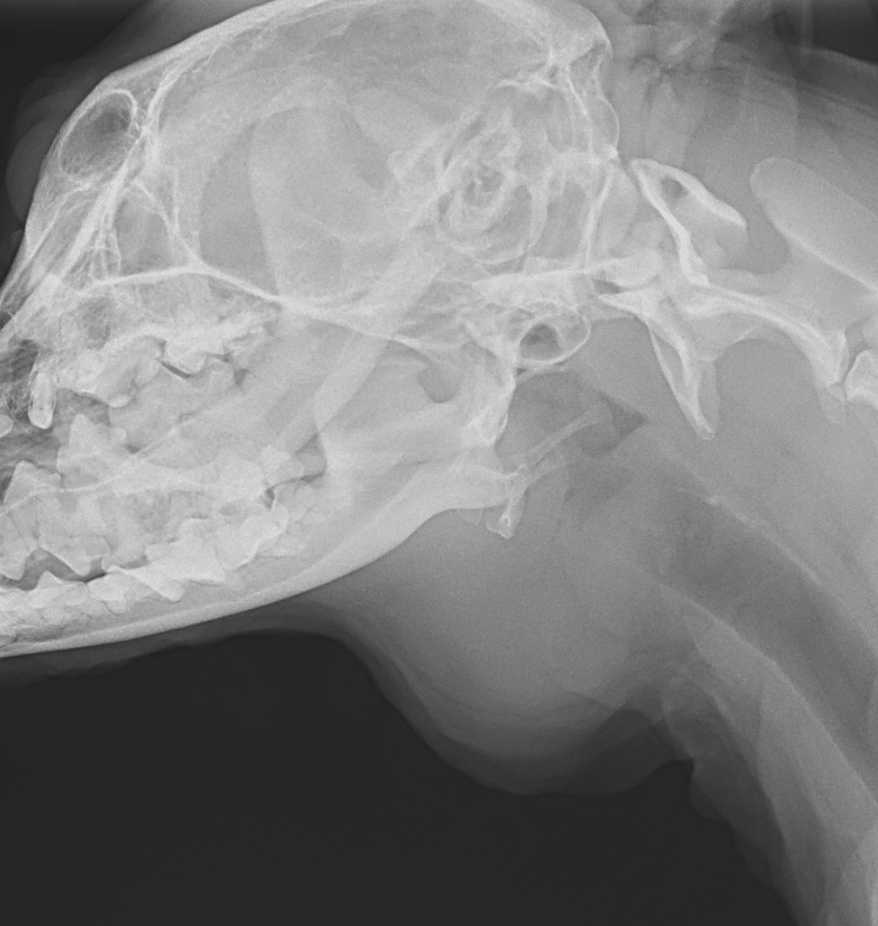

唾液腺嚢胞

高齢犬の頸部に腫瘤ができており、内部に唾液が溜まっているとのことで紹介がありました。

下顎には唾液腺が存在し、ここで作られた唾液が口の中へ分泌されます。唾液腺や、作られた唾液を運ぶ唾液腺管で損傷があると唾液が周囲に漏れて嚢胞を形成します。

根本的な治療として唾液腺ごと切除する方法があります。

この患者さんは切除後は再発もなく良好に経過しています。